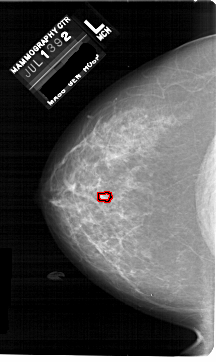

FILE: A_1742_1.LEFT_MLO.OVERLAY TOTAL_ABNORMALITIES 1 ABNORMALITY 1 LESION_TYPE MASS SHAPE LOBULATED MARGINS CIRCUMSCRIBED ASSESSMENT 4 SUBTLETY 2 PATHOLOGY BENIGN TOTAL_OUTLINES 1 BOUNDARY |

ics_version 1.0 filename A-1742-1 DATE_OF_STUDY 13 7 1992 PATIENT_AGE 48 FILM FILM_TYPE REGULAR DENSITY 3 DATE_DIGITIZED 3 3 1999 DIGITIZER HOWTEK 43.5 SEQUENCE LEFT_CC LINES 6871 PIXELS_PER_LINE 4096 BITS_PER_PIXEL 12 RESOLUTION 43.5 OVERLAY LEFT_MLO LINES 6871 PIXELS_PER_LINE 4666 BITS_PER_PIXEL 12 RESOLUTION 43.5 OVERLAY RIGHT_CC LINES 6871 PIXELS_PER_LINE 4306 BITS_PER_PIXEL 12 RESOLUTION 43.5 NON_OVERLAY RIGHT_MLO LINES 6871 PIXELS_PER_LINE 4606 BITS_PER_PIXEL 12 RESOLUTION 43.5 NON_OVERLAY |